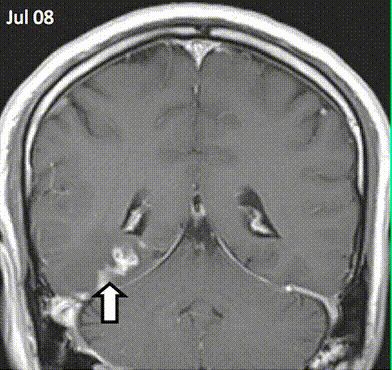

Τέσσερα χρόνια χρειάστηκαν μέχρι να ανακαλύψουν οι γιατροί τι συνέβαινε στο κεφάλι ενός 50χρονου κινέζου με περίεργα νευρολογικά συμπτώματα: ένα παρασιτικό σκουλήκι ταινία σερνόταν μέσα στον εγκέφαλό του. Το περιστατικό είναι σπάνιο, όχι όμως μοναδικό.